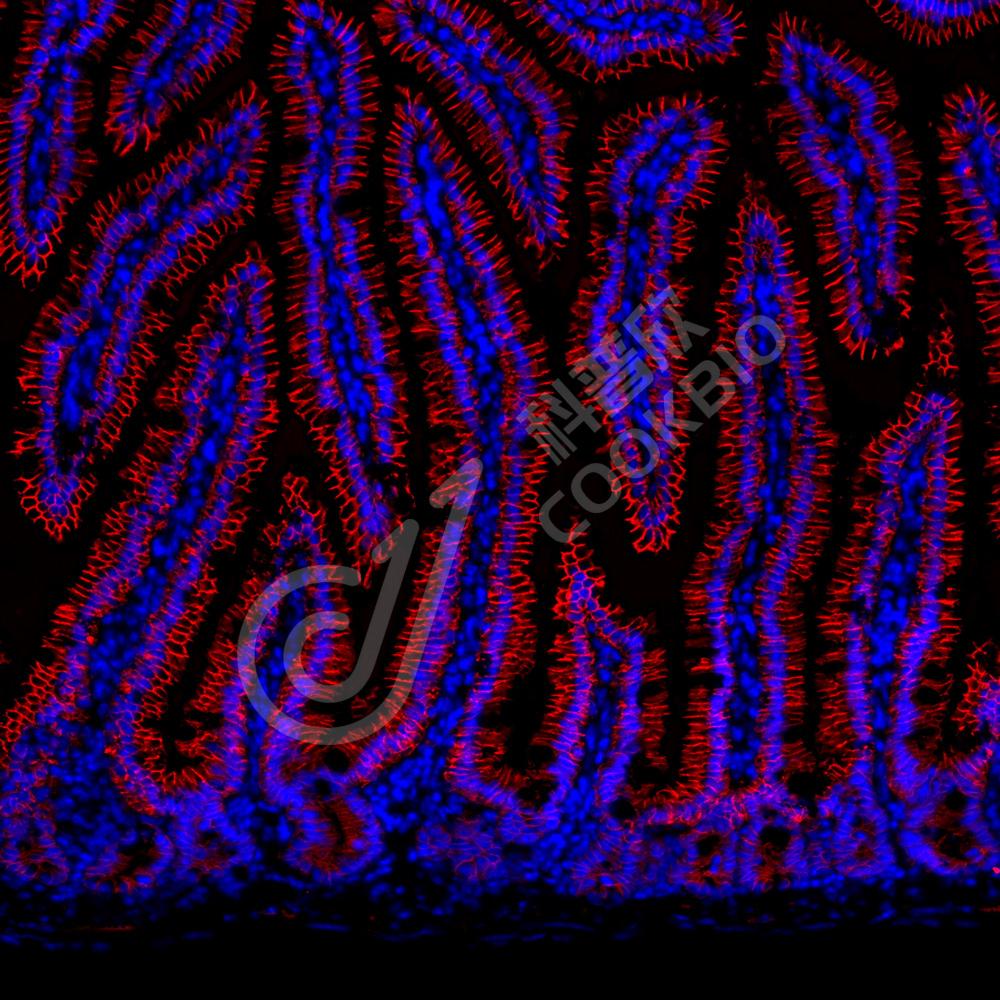

IF检测Sodium Potassium ATPase蛋白(货号 K134200-1)(红色).

样品: 小鼠小肠, 4%多聚甲醛 (货号KSG1101) 固定12-24小时.

抗原修复: Tris-EDTA抗原修复液(pH 9.0) (KSG1203), 98℃, 20分钟.

封闭: 3% BSA(货号KSGC305010)的PBS溶液, 室温孵育30分钟.

—抗: 1: 800稀释, 4℃ 孵育过夜.

二抗: Cy3标记山羊抗兔IgG (H+L) (货号KB63909), 1: 300稀释, 室温孵育1小时.